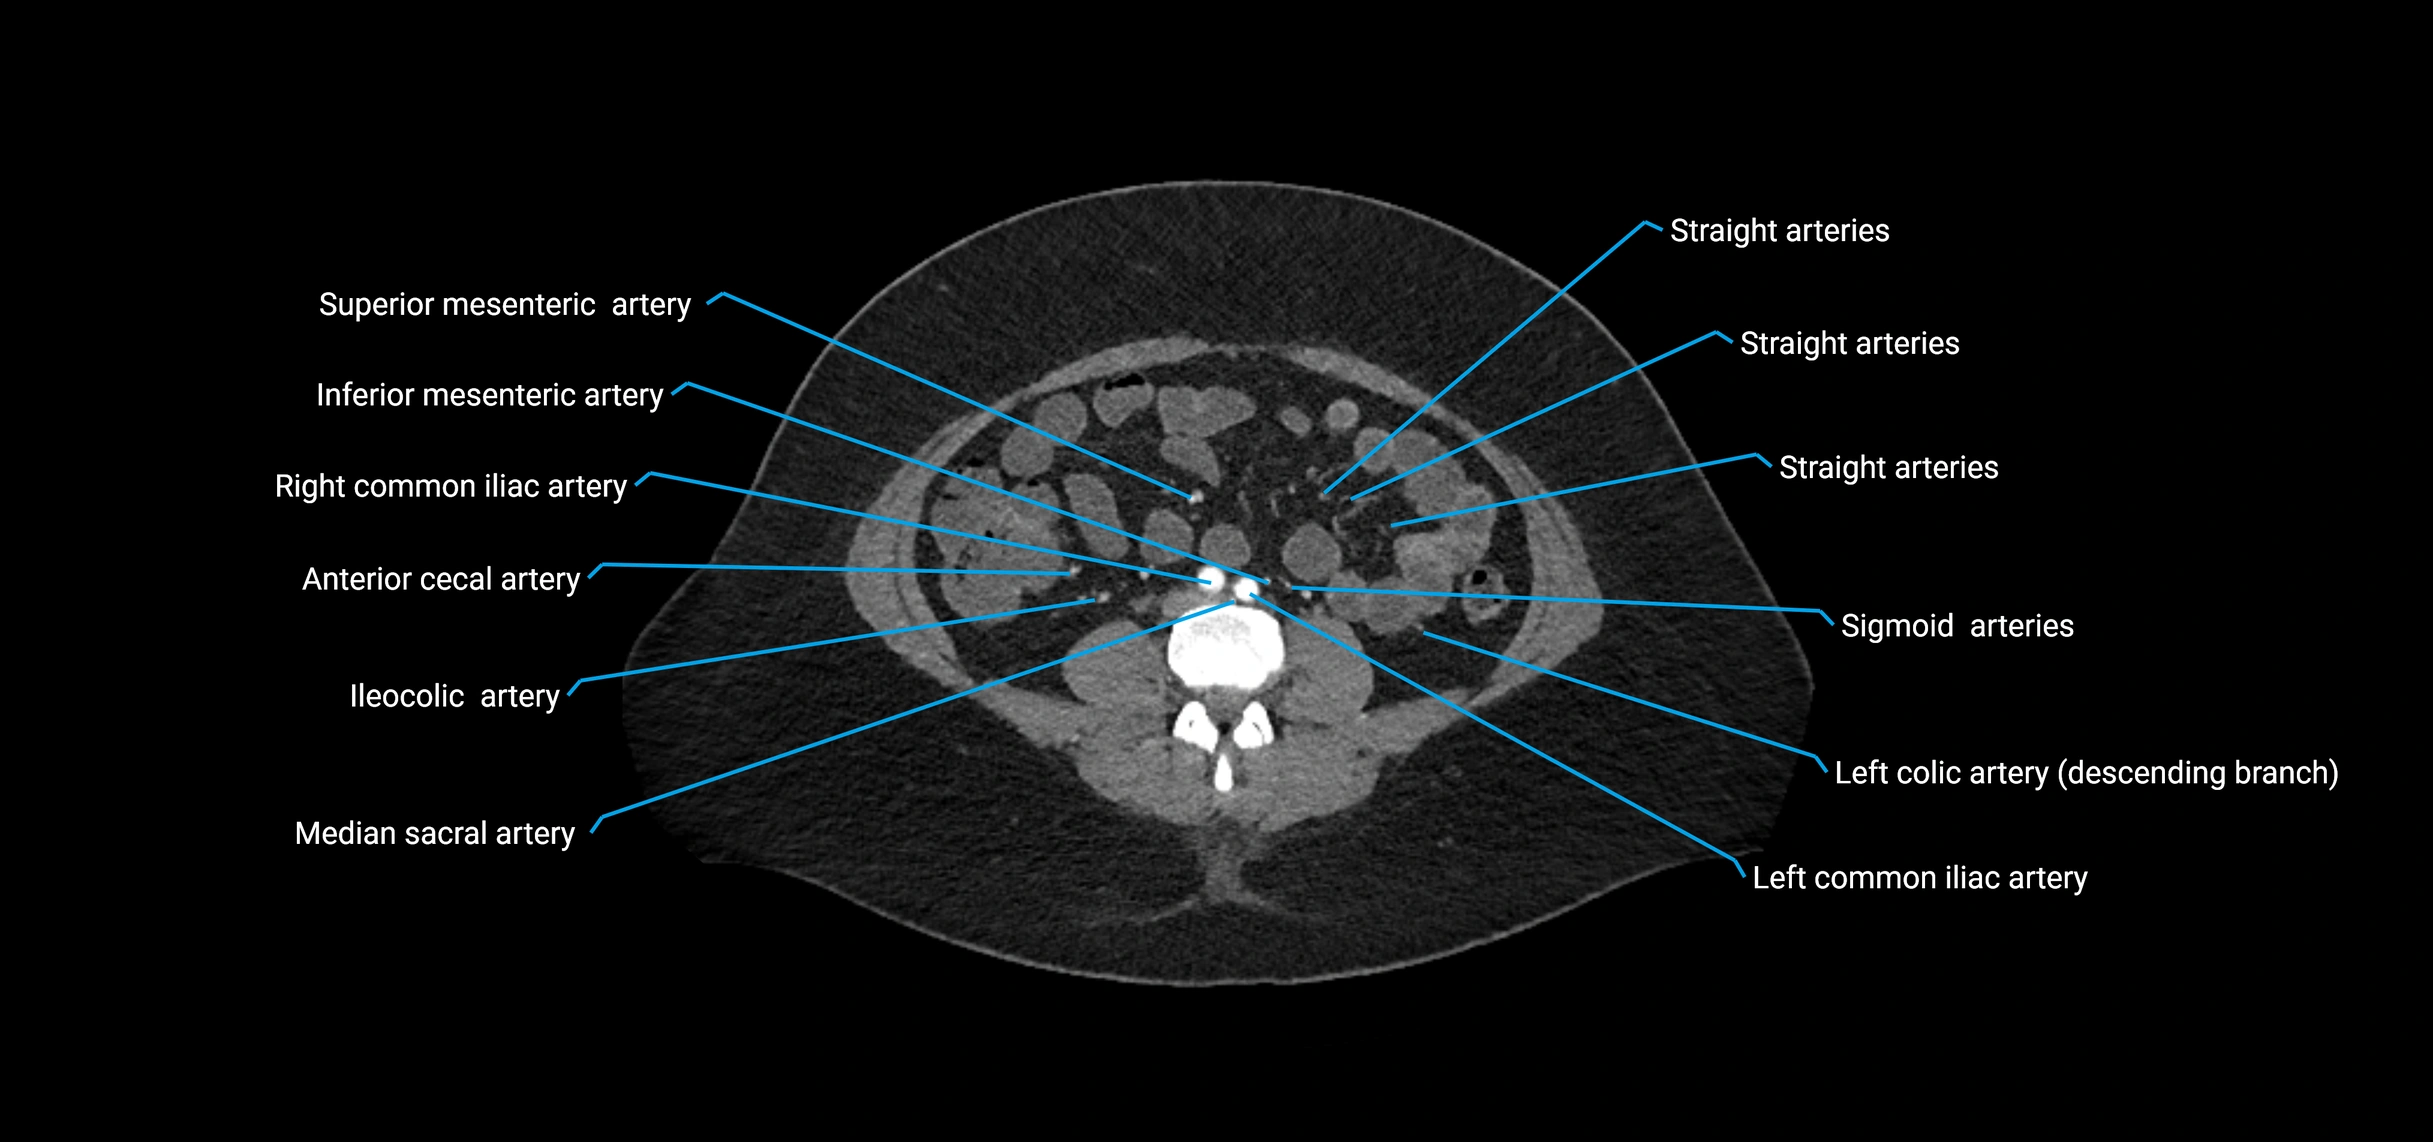

• Unpaired visceral branches: celiac trunk, superior mesenteric artery (SMA), inferior mesenteric artery (IMA)

• Paired visceral branches: middle suprarenal arteries, renal arteries, gonadal arteries (testicular or ovarian)

• Parietal branches: inferior phrenic arteries, lumbar arteries, median sacral artery

• Terminal branches: right and left common iliac arteries

Contrast-enhanced CT (CTA):

• Gold standard for abdominal aortic imaging

• Provides excellent detail of lumen, wall, aneurysm, thrombus, and branch vessels

• Multiplanar and 3D reconstructions help in aneurysm measurement, stent graft planning, and dissection evaluation

• Detects acute rupture, traumatic injury, or occlusion with high sensitivity